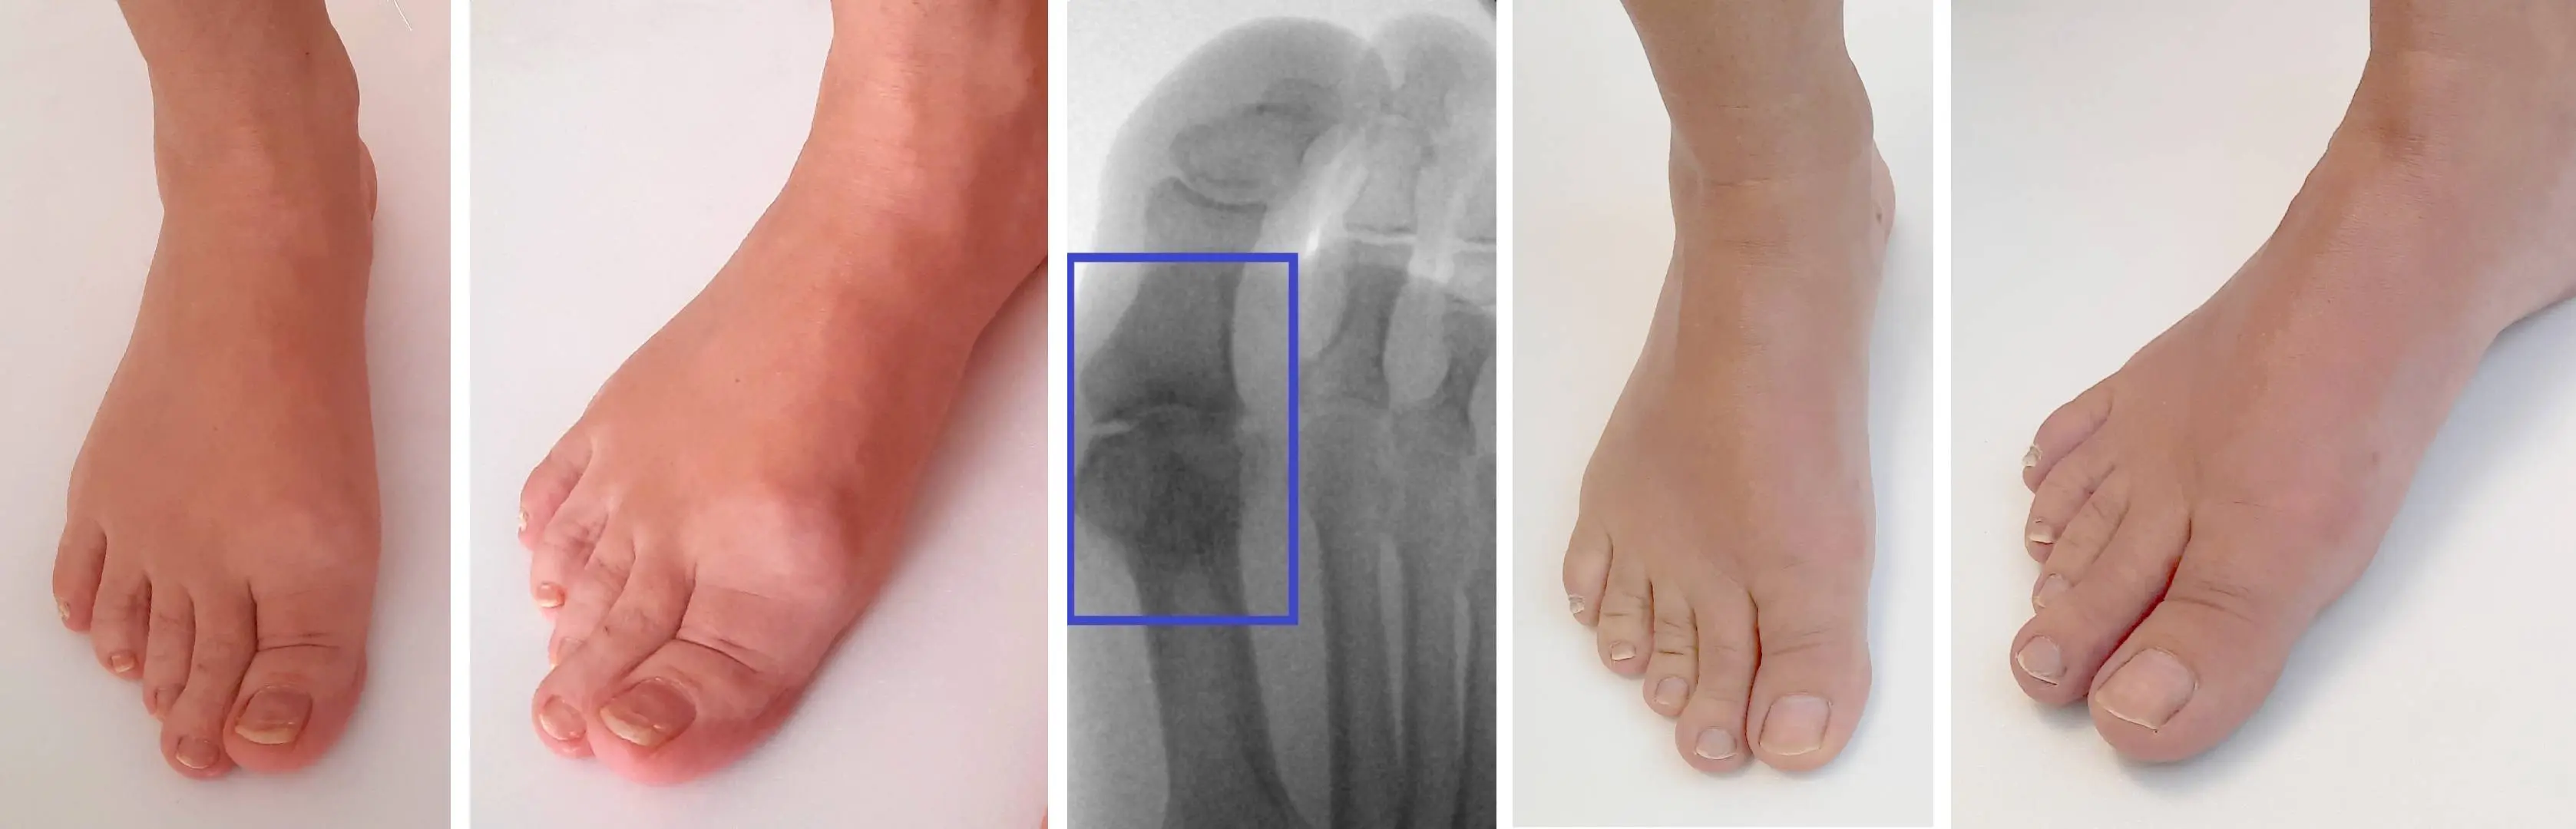

Obrázky: Vľavo predoperačné snímky. Možno vidieť zdurenie kĺbu spôsobené kostnými výrastkami. Stav je sprevádzaný bolesťou pri chôdzi, krívaním a obmedzením hybnosti. Uprostred na röntgenovej snímke sú zrejmé miernejšie artrotické zmeny, kostné výrastky a úbytok chrupavky kĺbu. Vpravo pooperačné fotky 4 mesiace po operácii. Kostné výrastky sú odstránené a obnovená hybnosť v kĺbe. Pooperačne takmer nepoznateľná jazva na vnútornej strane palca.